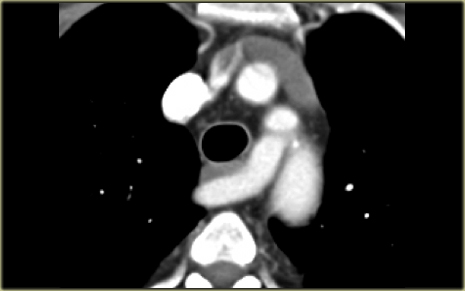

Describe the images on the left and then continue reading.

On the left side there is a vascular structure, that runs inferiorly below the level of the left hilum and enters into a dilated coronary sinus.

The diagnosis is left or double superior vena cava.

Left Superior Intercostal Vein.

This is an anastomosis between the accessory hemiazygos vein and the left brachiocephalic vein.

It courses along the lateral margin of the aortic arch (‘aortic nipple’).

It is a normal variant and if you look for this structure you will frequently notice it.